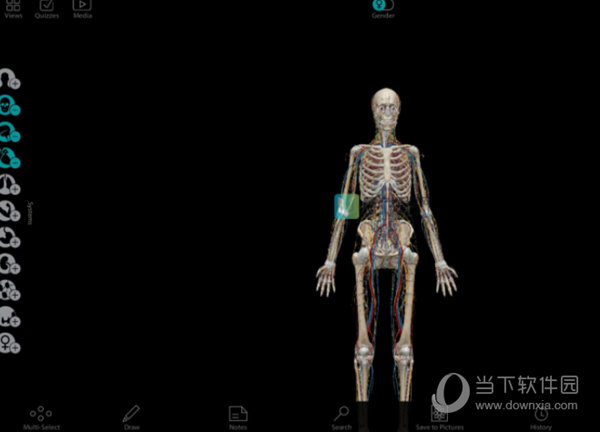

3、点击添加了神经系统的构成,可以清楚看到人体的神经系统构成。

4、添加了循环系统,使人体更加清晰。

5、添加了呼吸系统和肌肉系统,人体更加清楚。

6、添加了泌尿、消化等系统使人体更加完整。